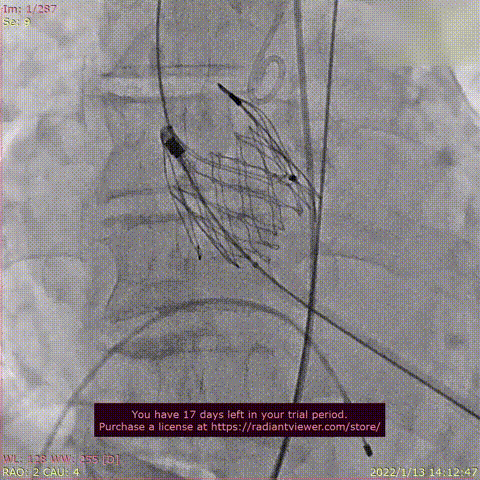

瓣膜释放过程

术后DSA影像图